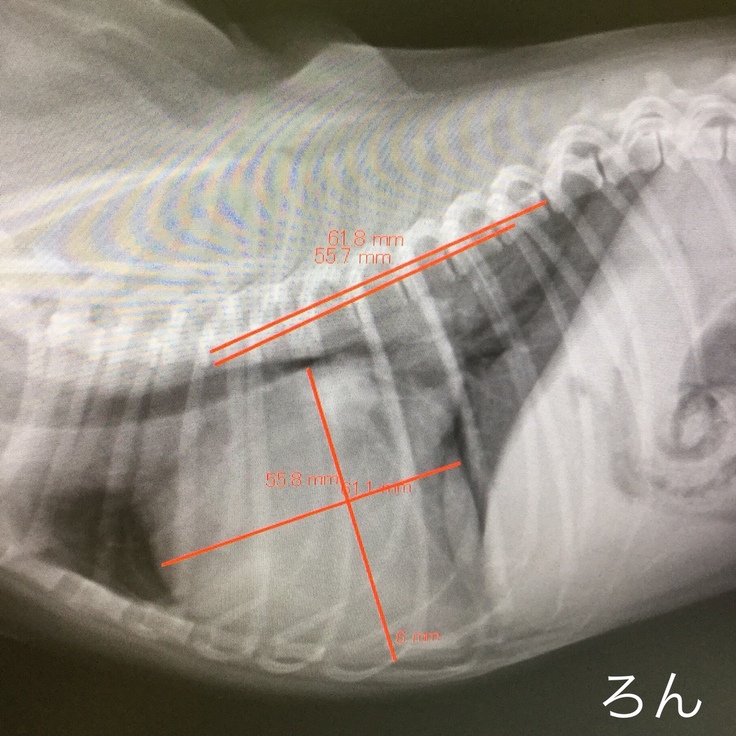

こちらは9月11日の心臓検査の診察結果です。写真を比較していただくと、心臓が大きく肥大しており気管を圧迫しているのが分かります。

肥大したろんの心臓

↑10月8日の心臓の検査でさらに心臓が肥大している事が分かりました。